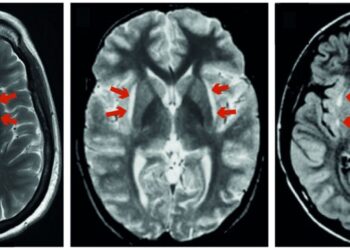

Um novo artigo de revisão, publicado na revista Brain , mostrou que uma região mal compreendida do cérebro chamada claustrum pode desempenhar ...